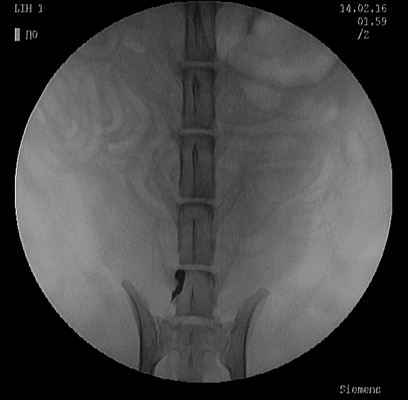

‣心血管造影検査について

心疾患の多くは心エコー検査で非侵襲的に診断が可能であるものの、非侵襲的な心臓検査のみでは診断が下せなかった場合、もしくは先天性心疾患(動脈管開存症ならびに肺動脈弁狭窄症)の診断・治療を行う際に追加検査として実施します。

‣心血管造影検査の方法

全身麻酔下にて透視X線装置と特殊なカテーテルを使用して検査を実施します。

正常:右心系

正常:左心系

動静脈瘻

動脈管開存症